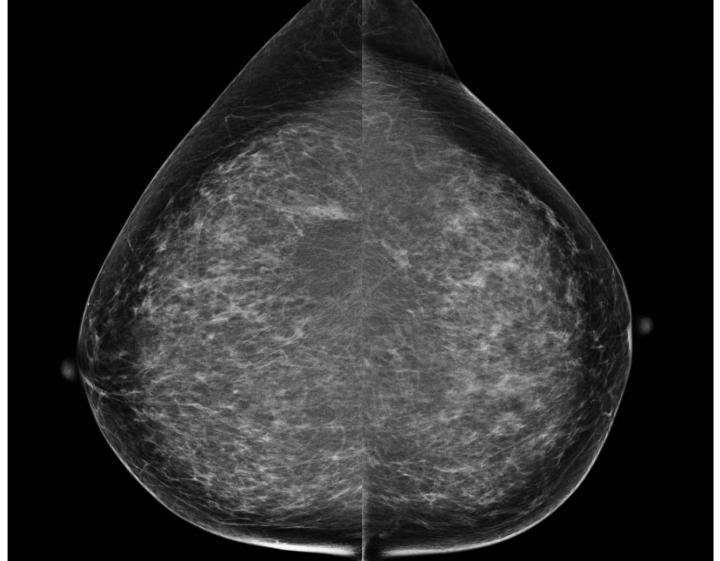

This is a screening mammogram demonstrating calcifications in the upper outer left breast. Bilateral cranio-caudal views shown here.

(Photo Credit: RSNA)